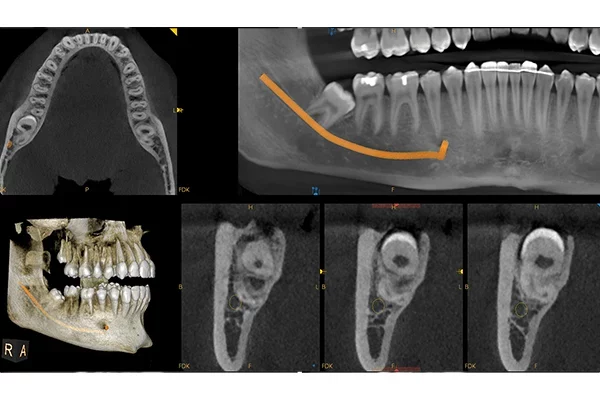

• Nové Crosss section zobrazení

• Automatické vytvoření OPG pohledu z CBCT skenu

• Automatický maping mandibulárních kanálů